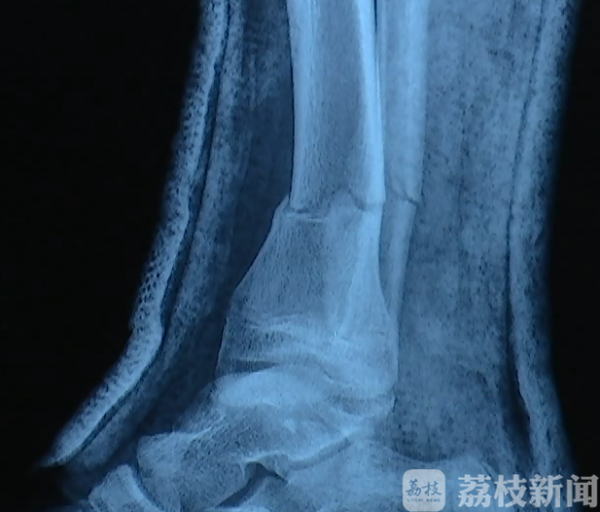

胡先生赶到医院后,发现儿子右腿被撞伤,医生拍片后诊断为:右胫腓骨远端粉碎性骨折。从片子上也明显能看到,距离脚踝两公分处,骨头明显断裂。在医生的建议下,小宇回家休养,进行保守治疗。事后胡先生了解到,小宇是被校园保安骑电动车撞伤的,监控也拍下了这一幕。